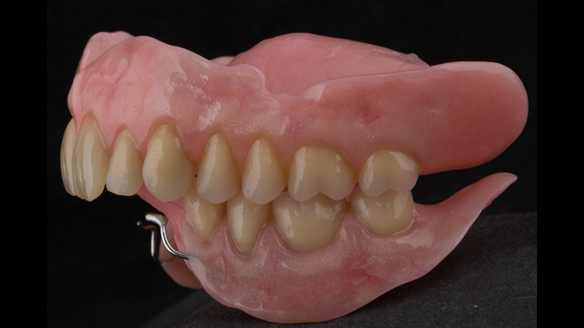

This newsletter describes in step by step detail the transition from acrylic based immediate dentures to metal based definitive dentures.

- Definitive dentures (Mk 2) – complete upper metal reinforced and lower cobalt chromium based partial of hygienic Scandinavian design to be made 9 - 12 months after extractions of all upper teeth and LR5 and LL4